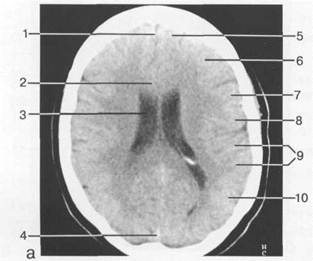

Рис. 1.12. Уровень хиазмальной (супраселлярной цистерны): а — аксиальный срез КТ; б — аксиальный срез МРТ (Т2-ВИ).

1 — внутренняя сонная артерия; 2 — миндалевидное тело; 3 — мост; 4 — хиазма; 5 — спинка турецкого седла; 6 — базилярная артерия; 7 — боковая цистерна моста; 8 — передняя мозговая артерия; 9 — сред­няя мозговая артерия; 10 — задняя соединительная артерия; 11 — ножка мозга; 12 — четверохолмие; 13 — бугорок турецкого седла; 14 — воронка; 15 — хиазмальная цистерна; 16 — задние мозговые артерии; 17 — межножковая цистерна; 18 — охватывающая цистерна.

Сразу над турецким седлом расположена супраселлярная цистерна в виде правильной фор­мы четырехугольника, а чаще пятиугольника (рис. 1.12). Весьма важной при анализе супрасел­лярной цистерны является оценка симметричности изображения ее крыльев. Малейшая асим­метрия должна быть тщательно зафиксирована в протоколе, так как подобные изменения мо­гут быть манифестацией развивающегося поперечного смещения. На тонких срезах в передних отделах супраселлярной цистерны удается проследить перекрест зрительных нервов. Еще вен-тральнее расположена линейной формы терминальная цистерна, ориентированная в передне-заднем направлении по срединной сагиттальной линии.

В верхнецентральных отделах супраселлярного региона часто удается проследить изобра­жение гипоталамуса, имеющего вид двух треугольников, основаниями ориентированных кпе­реди. На этом уровне начинают прослеживаться нижние отделы III желудочка. Описанные выше ликворсодержащие структуры называют срединными. К ним также относят серповид­ный отросток твердой мозговой оболочки, прозрачную перегородку, эпифиз. III желудочек наиболее удачно представлен на следующем срезе (см. рис. 1.10). Его стенки должны быть рас­положены параллельно относительно друг друга, допускается их легкое выбухание или вог­нутость, но ширина в норме не превышает 4 мм для обследуемых любого возраста. Впереди III желудочка в виде симметричных дугообразно изогнутых ликворсодержащих структур про-